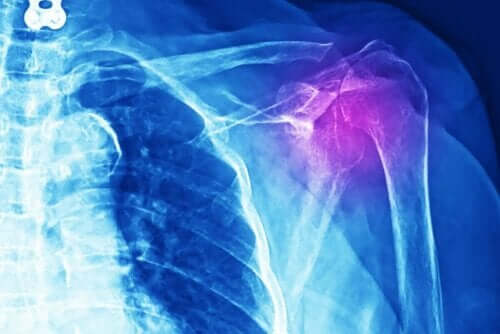

يجب على الأطباء إجراء فحوصات مختلفة لتشخيص هذا النوع من الإصابات. تشمل تلك الفحوصات الأشعة السينية، أو الموجات فوق الصوتية، أو التصوير بالرنين المغناطيسي، أو التصوير المقطعي المحوري المحوسب (الأشعة المقطعية). علاوة على ذلك، يجب عليهم إجراء فحص طبي ودراسة التاريخ الطبي للمريض بشكل مفصل.

توفر الأشعة بيانات مهمة لتقييم شدة التهاب أوتار الكتف.